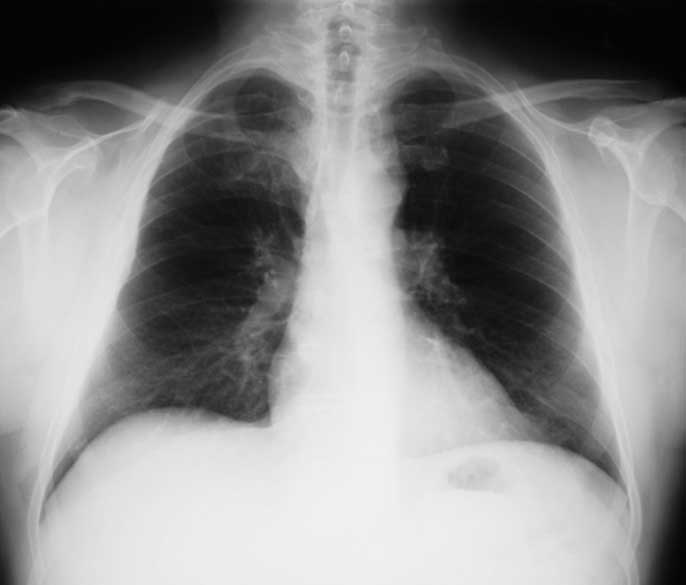

Researchers at UC Davis have found that the investigational cancer vaccine tecemotide, when administered with the chemotherapeutic cisplatin, boosted immune response and reduced the number of tumors in mice with lung cancer. The study also found that radiation treatments did not significantly impair the immune response. The paper was published on March 10 in the journal Cancer Immunology Research, an American Association for Cancer Research (AACR)publication.

Though tecemotide, also known as Stimuvax, has shown great potential at times, the recent Phase III trial found no overall survival benefit for patients with non-small cell lung cancer (NSCLC). However, further analysis showed one group of patients, who received concurrent chemotherapy and radiation followed by tecemotide, did benefit from the vaccine. As a result, tecemotide’s manufacturer, Merck KGaA, is sponsoring additional post-clinical animal and human studies, so far with good results.